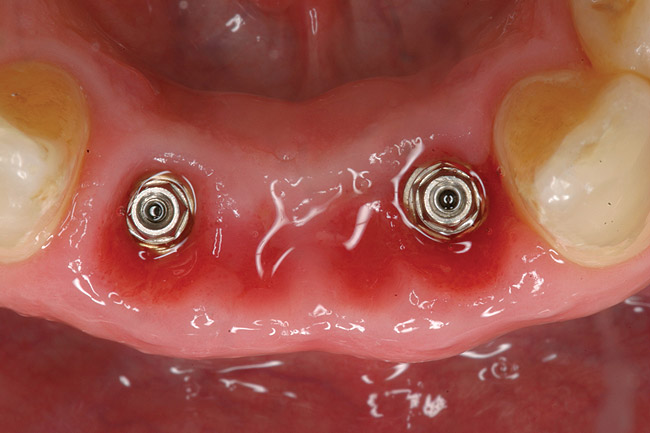

The patient was given postoperative instructions and advised to maintain a soft diet for 6 to 8 weeks to protect the implants. The patient was followed weekly for the first 3 weeks and monthly thereafter. After 4 months of healing, the provisional restoration was removed and the soft tissues were examined. Mature, keratinized gingival tissues were present facially, lingually, and interproximally. Nonkeratinized tissue could be seen at the tissue surfaces of the ovate pontics and in the intrasulcular regions of the implant abutment units. No clinical probing depths beyond 1 mm were found adjacent to the abutments. The healed tissue represented an acceptable clinical result especially in light of the gap that had been present at the time of implant placement (Figure 7A and Figure 7B). Final impressions were made, and the permanent ceramo-metal screw-retained prosthesis was placed within 8 weeks (Figure 8).

Figure 7b  Clinical healing completed.

Figure 7b